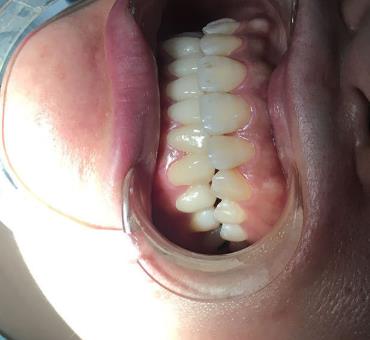

牙齒矯正案例展示:

因為我的牙齒不整齊的問題,小的時候經(jīng)常受到朋友的譏笑,導(dǎo)致我特別的自卑,那時候也想過去醫(yī)院做牙齒矯正手術(shù),但是由于我的家庭條件不是很好,拿不出那么多的錢去醫(yī)院做牙齒矯正手術(shù),所以這個想法就沒有。等我上了班以后,錢包里有了些積蓄,我要做的第一件事情,就是去醫(yī)院做牙齒矯正手術(shù)。有了想做牙齒矯正手術(shù)的想法,就開始在網(wǎng)上查詢當(dāng)?shù)氐目谇会t(yī)院,我想在當(dāng)?shù)刈鍪中g(shù),比較方便以后復(fù)診。四川省人民醫(yī)院口腔科

經(jīng)過慎重的對比后,我覺得四川省人民醫(yī)院口腔科較為正規(guī),口碑也不錯,就預(yù)約了手術(shù)時間,來四川省人民醫(yī)院口腔科做牙齒矯正手術(shù)了。面診了醫(yī)生以后,李崢醫(yī)生給我看了他做的許多成功的牙齒矯正案例,我也問了很多手術(shù)問題,李崢醫(yī)生都有耐心的一一解答,回答的很專業(yè),提出的建議也很中肯。

李崢醫(yī)生說像我牙齒的情況,不適合帶隱形牙套,給我推薦了一種3m自鎖托槽牙套,這種牙套戴在牙齒的里面,別人也不會發(fā)現(xiàn)做了牙齒矯正手術(shù)。瞬間覺得李崢醫(yī)生的醫(yī)德特別高尚,并不會因為賺錢而推薦價錢小貴的隱形牙套。

兩周以后,我就帶上了牙套。剛帶上牙套那會,我的很不舒服,牙套磨嘴不說,牙齒酸軟無力,我堅持了一周左右,牙齒就變得舒服多了。

這個牙套我?guī)Я艘荒臧氲臅r間,就成功的摘掉了,現(xiàn)在牙齒變得又整齊又潔白,整個人不但變漂亮了,而且變得更加有自信,無論做什么事情都充滿了熱情。我較為的開心。